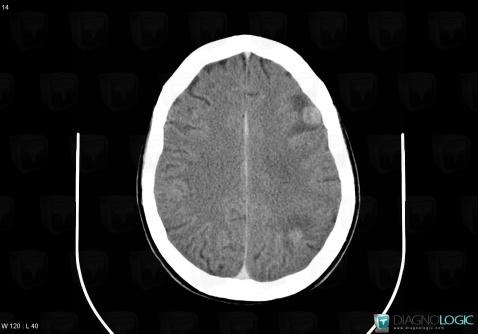

Toxoplasmosis, Cerebral hemispheres, CT

Here is the specific information in the key image above:

- Diagnosis Toxoplasmosis (link to Abscess), Location(s) Cerebral hemispheres, with gamuts Intracerebral lesion with ring enhancement, Intracerebral lesion with moderate enhancement, Multifocal intracranial lesions